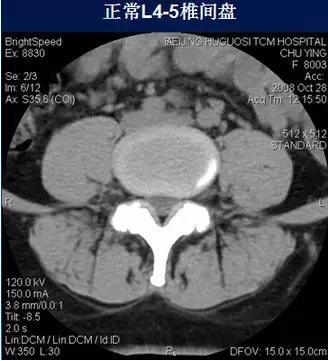

常规腰椎CT扫描层面

常规腰椎CT扫描L3-S1段,分为

(2)椎间盘层面(软组织窗):观察椎间盘、硬膜囊、神经根、韧带等软组织。

二、椎间盘膨出

椎间盘影均匀超出相应椎体边缘,轻度时CT表现为间盘后缘正常肾形凹陷消失,圆隆饱满。